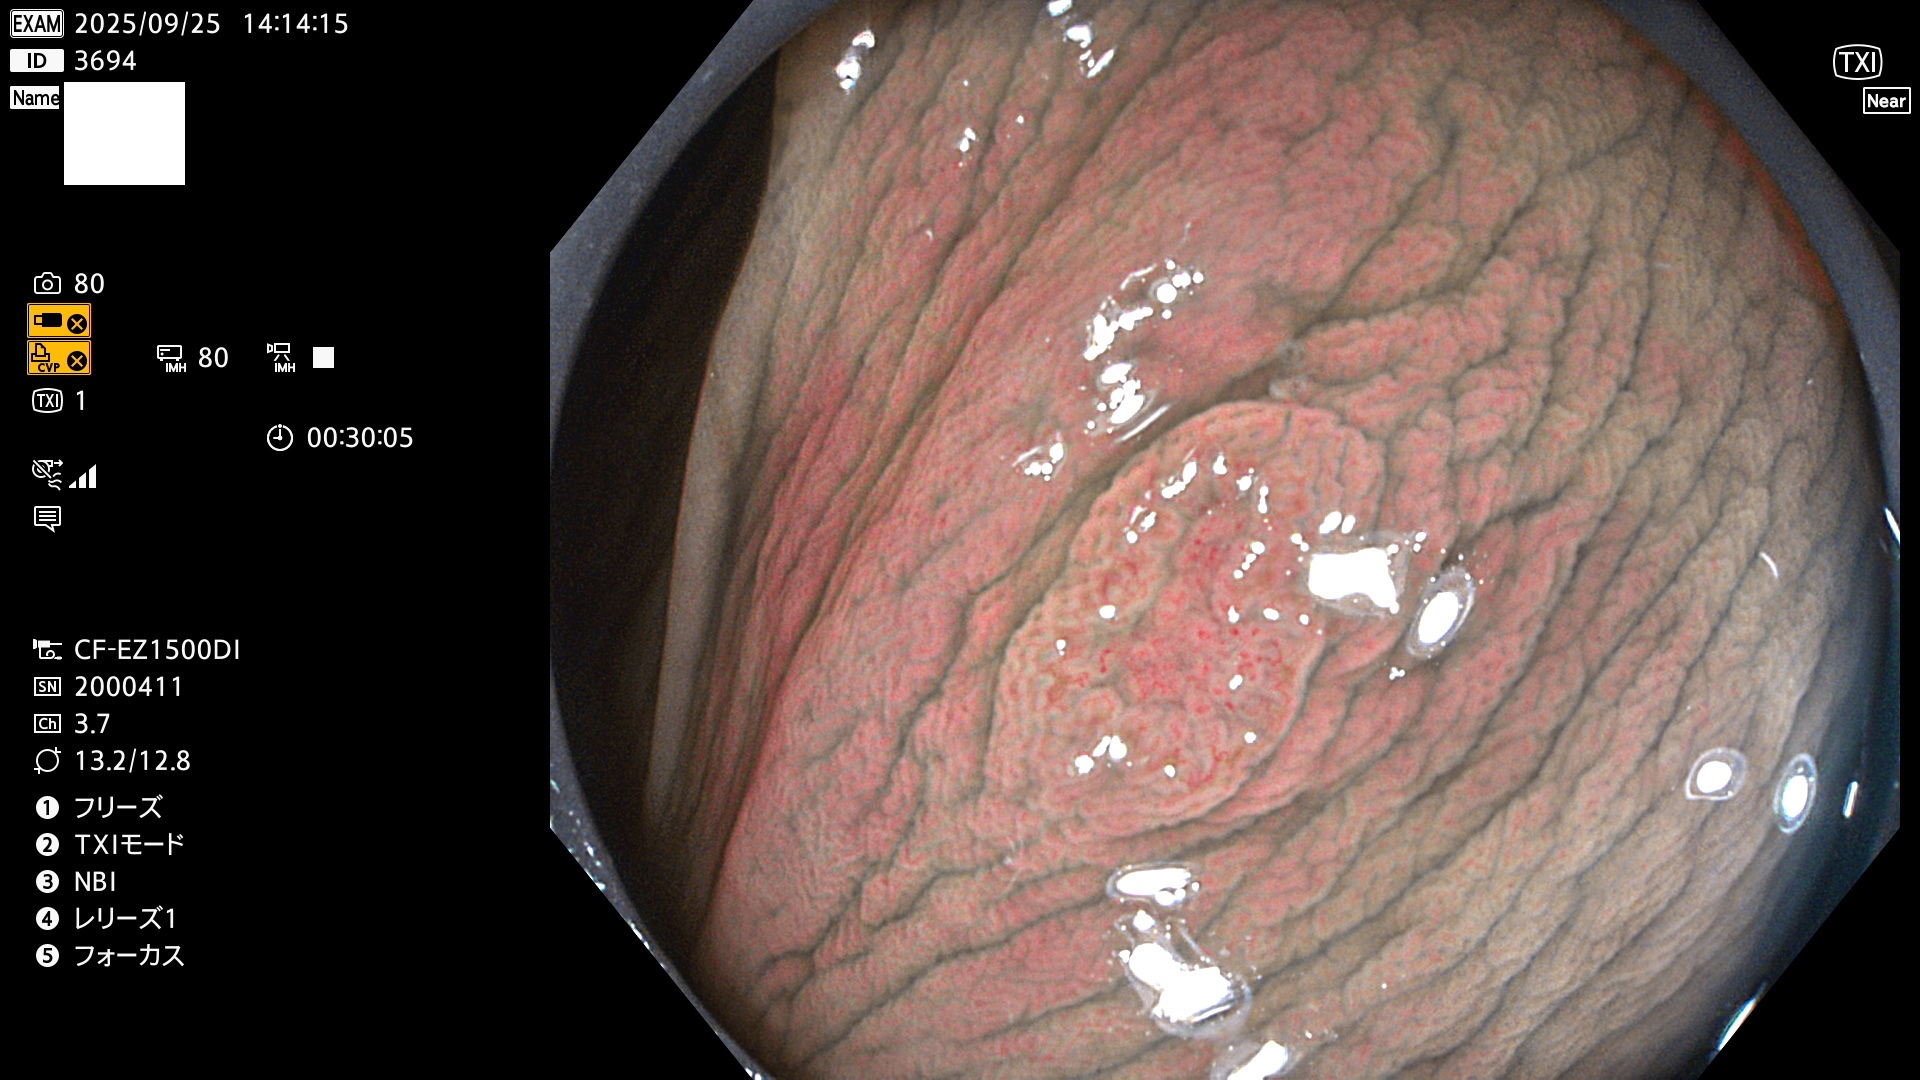

完全に平坦な物をUb、陥凹している物をUcと呼びます。Ubは認識が困難で、Ucはびらん(炎症)と紛らわしいために見落とされやすく、「内視鏡後・大腸癌」の原因になります。

専門的)Uc=De Novo癌? 内視鏡の解像度が低かった時代、このような説もありました。しかし今日の高精度内視鏡では良性の微小なUc型腺腫(APC遺伝子異常の腺腫)が日常的に見つかります。Ucこそが多段階発癌(Adenoma-Carcinoma Sequence)のMain Routeです。

毎週の検査(木・金・土・日)に発見されたUbとUc型・腺腫を、その週の日曜の夜にUPし1週間、提示します。

2025年9月25日〜9月28日の4日間(40件)4個 (Uc_ADR=4個/40人=10%)

2025年9月25日〜9月28日の4日間(40件)で4個 (Uc_ADR=4個/40人=10%)